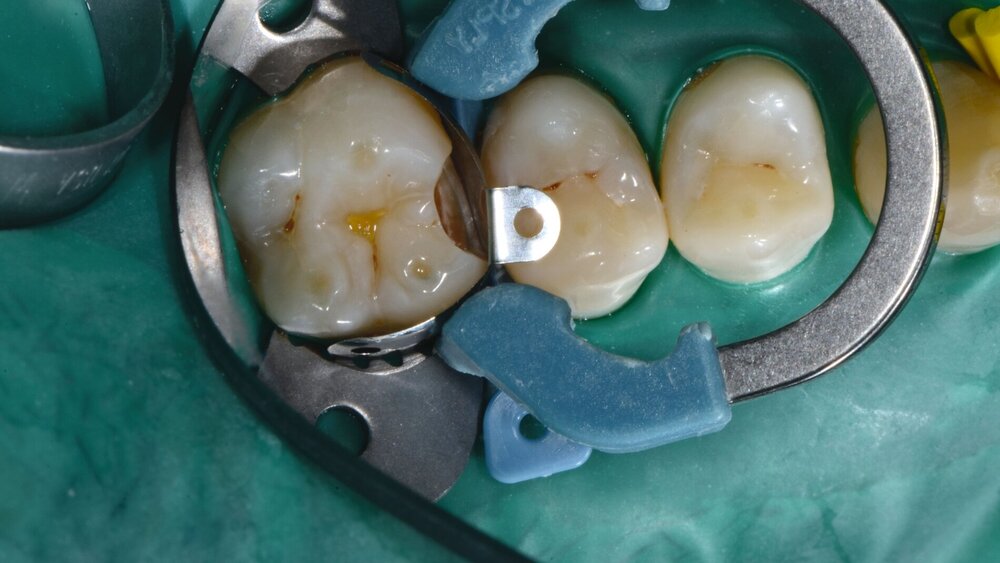

Die Matrizentechnik ist entscheidend für die Abdichtung der Kavität im Sinne einer Trockenlegung sowie für die Konturierung des Restaurationsmaterials und eine suffiziente approximale Kontaktpunktgestaltung. Je nach klinischem Szenario kann man aus verschiedenen Materialien und Techniken auswählen. Zur Auswahl der Art der Matrize lagen nur wenige In-vivo-Studien vor, wobei berichtet wurde, dass sowohl Metall- als auch Kunststoffmatrizen für eine ausreichende Approximalkontaktgestaltung verwendet werden können [Cenci et al., 2007; Demarco et al., 2007; Demarco et al., 2011; Prakki et al., 2004]. In-vitro-Untersuchungen deuten darauf hin, dass bei der Verwendung von vorgeformten Teilmatrizen zur Herstellung von Klasse-II-Restaurationen eine bessere approximale Kontaktpunktfestigkeit, weniger Randüberschüsse und stabilere Randleisten erzielt werden können (Abbildung 1) [Loomans et al., 2006; 2008; 2009; Saber et al., 2011; 2010].